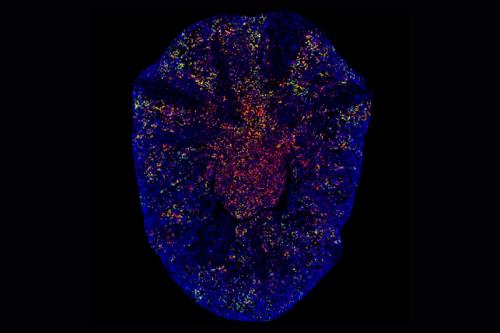

- Identifying metabolic defects that limit tissue repair in the heart and other organs

- Uncovering the role of the extracellular matrix in regulating the degree of fibrosis Excessive scarring within an organ due to disrupted healing. It can lead to organ dysfunction and is associated with conditions like chronic kidney disease, liver cirrhosis and heart failure. fibrosis Excessive scarring within an organ due to disrupted healing. It can lead to organ dysfunction and is associated with conditions like chronic kidney disease, liver cirrhosis and heart failure.

- Developing therapies to promote tissue regeneration and repair